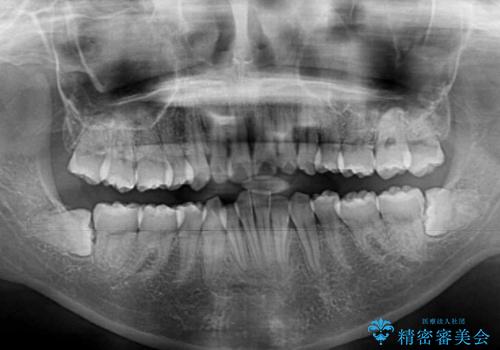

- 以前の矯正治療の後戻りにより、上下の前歯がでこぼこになってしまったことを気にして来院された患者様です。

口元がこれ以上突出することなく前歯の叢生が改善できるよう、歯と歯の間を削ってスペースを獲得し、インビザラインを用いて整えていくこととしました。